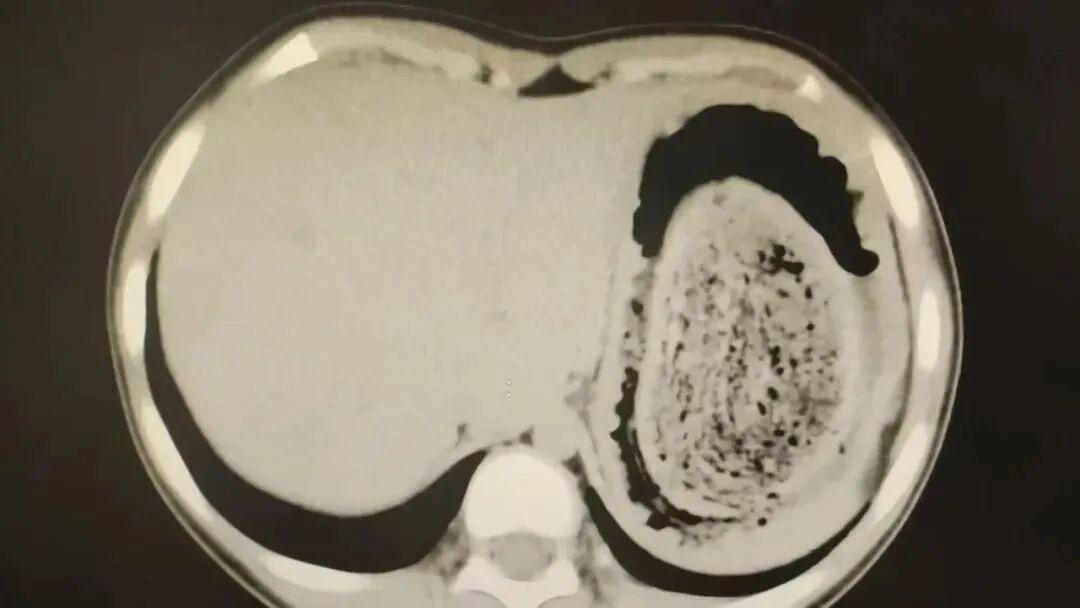

近日,25岁的杭州姑娘佳佳(化名)前往浙江大学医学院附属第一医院,她已经腹胀了三四个月,肚子摸上去硬得像块石头,连饭都吃不下。医生本以为是普通的胃肠疾病,然而,当胃镜探头进入胃部,视野瞬间被堵死,一幕令人头皮发麻。整个胃部被一团密密麻麻的异物塞满,成团的异物包块表面,全是密密麻麻的头发。由于头发无法被胃液消化,也很难把它们排出去。在胃酸的作用下,头发与食物残渣及其他胃内容物混合,像滚雪球似的越变越大、越变越硬,逐渐形成坚硬的“胃石”,在临床上称为“毛石症”。

这颗胃石几乎把整个胃腔都占满了。医生花了一个多小时将其分解,取出有整整近2斤。目前佳佳恢复良好。